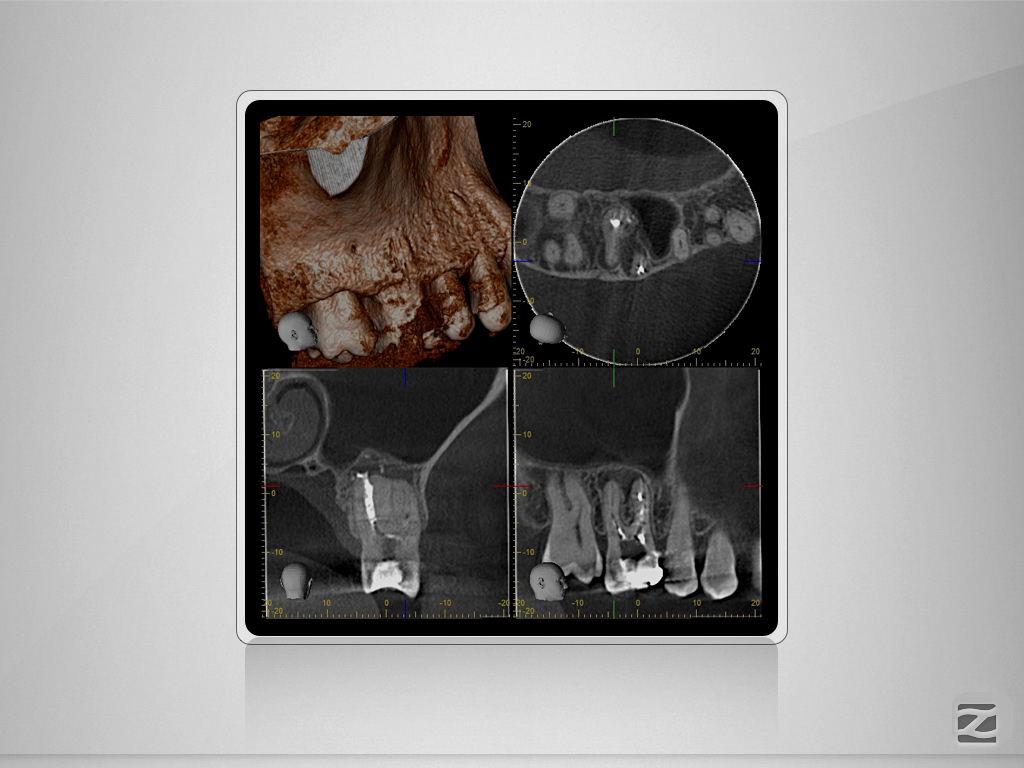

16D.004

Multiple Fragmente